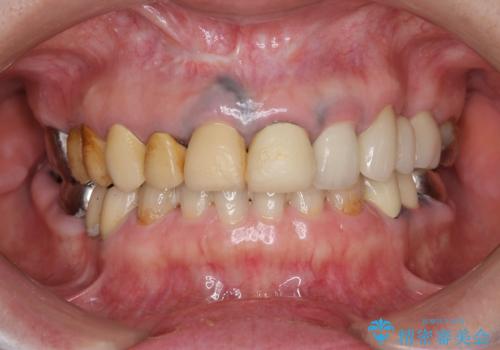

10数年前に治療を行った保険適応の硬質レジン前装冠は変色劣化が進み、審美的に問題があるだけでなく虫歯のリスクも高くなり好ましくない状況です。

- 39.6万円(ジルコニアクラウン×3・仮歯×3)費用は治療当時の料金となります